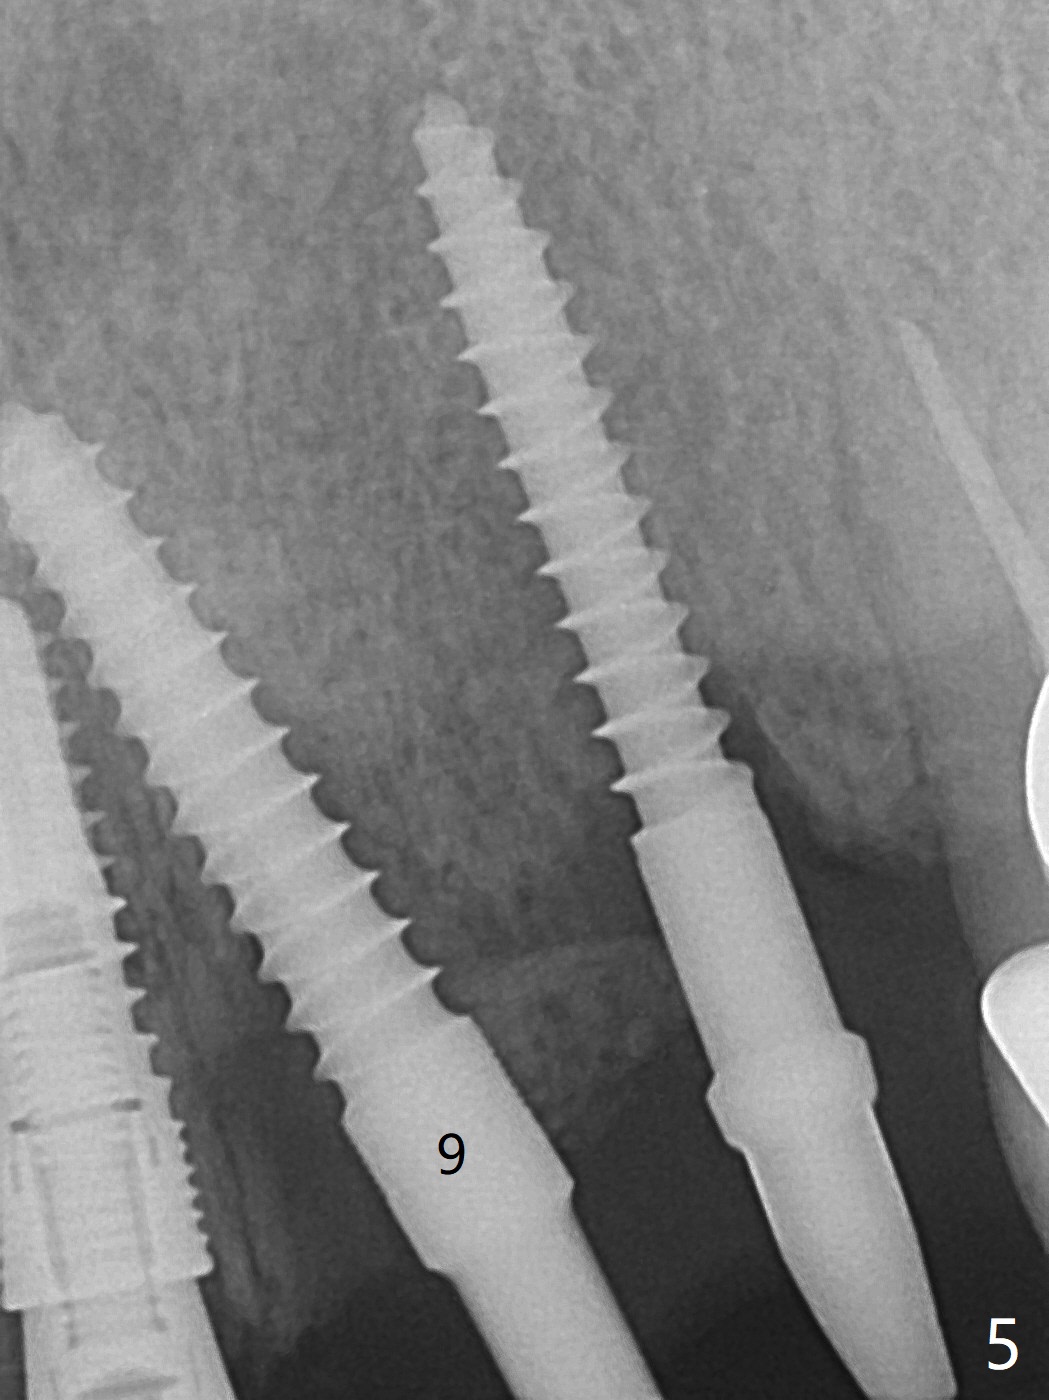

Incision shows exposure of microthreads at #9 and major threads at #10 due to buccal placement (Fig.1). There is bone palatal to the implant at #10 (Fig.2 P), to which a new implant will move. After implant removal, a narrower 1-piece implant (2.5x14(4) mm) is placed palatally at #10 (Fig.3,4) in combination of guide and free hand. At the site of #9 after implant removal, the guide is not used; a 3x17 mm angled 1-piece implant is placed with bad trajectory (Fig.5,6). After re-adjustment (Fig.7), the implant is placed at the right orientation (Fig.8). It appears that the guide is helpful. Allograft is placed mainly buccally (Fig.9,10 *), followed by a piece of collagen membrane (Fig.11). After tension release, flaps are approximated (Fig.12). The buccal gingiva at #9 and 10 recede nearly 2 months postop (Fig.13). Less recession at #9 is associated with more inflammation (Fig.14). The margin of the provisional is adjusted for gingival margin down growth and easy self cleaning with Water Pik (Fig.15). One month later, the gingival inflammation reduces, while there is no obvious buccal collapse (Fig.16,17). Impression is taken after laser gingivectomy nearly 4 months postop (Fig.18). While the gingiva around the implant at #9 is inflamed (periimplantitis?), the gingival cuff at #10 is well formed 5.5 months postop immediately before cementation (Fig.19). The buccal concavity at #10 is minimal (Fig.20). The gingival inflammation at #9 will be hopefully resolved after cementation of the final restorations (Fig.21). There appears to be new bone formation around the coronal implant threads 5.5 months postop (immediately post cementation, Fig.22). The microthreads at #9 may be not covered by the bone, the reason for the gingival erythema. The redness at #10 is asymptomatic 5.5 months post cementation (Fig.23). 粘固后两年牙槽嵴骨质并没有再生(图二十四),说明第一术中植体必须植入骨下(基台部分要长,否则难于修复),第二牙槽嵴处不应该有压力,植入2.5毫米植体,最后钻头应该是2.5毫米,骨下1-3毫米(尝试项目)。